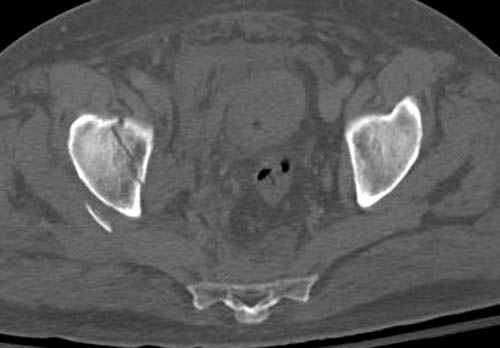

Дополнительно имеется перелом ацетабулума: задняя

колонна с полупоперечным переломом, и переломы костей лица.

На седьмой день зафиксирован перелом ацетабулума через задний доступ. Перед операцией для профилактики DVT, IVC фильтер, также получает Lovenox.

Латеральное положение облегчает проведение тракции через вертел, за 5 мм стержень за вертел (грузом через тракционное приспособление), на обычном рентгенопрозрачном операционном столе, а для положения на животе, наверное, Judet Table более приемлем, потому что там имеется латеральное тракционное устроиство.

Там множество обычных 2.7 мм шурупов, потом идет фиксация основными пластинами.

Снимки здесь....